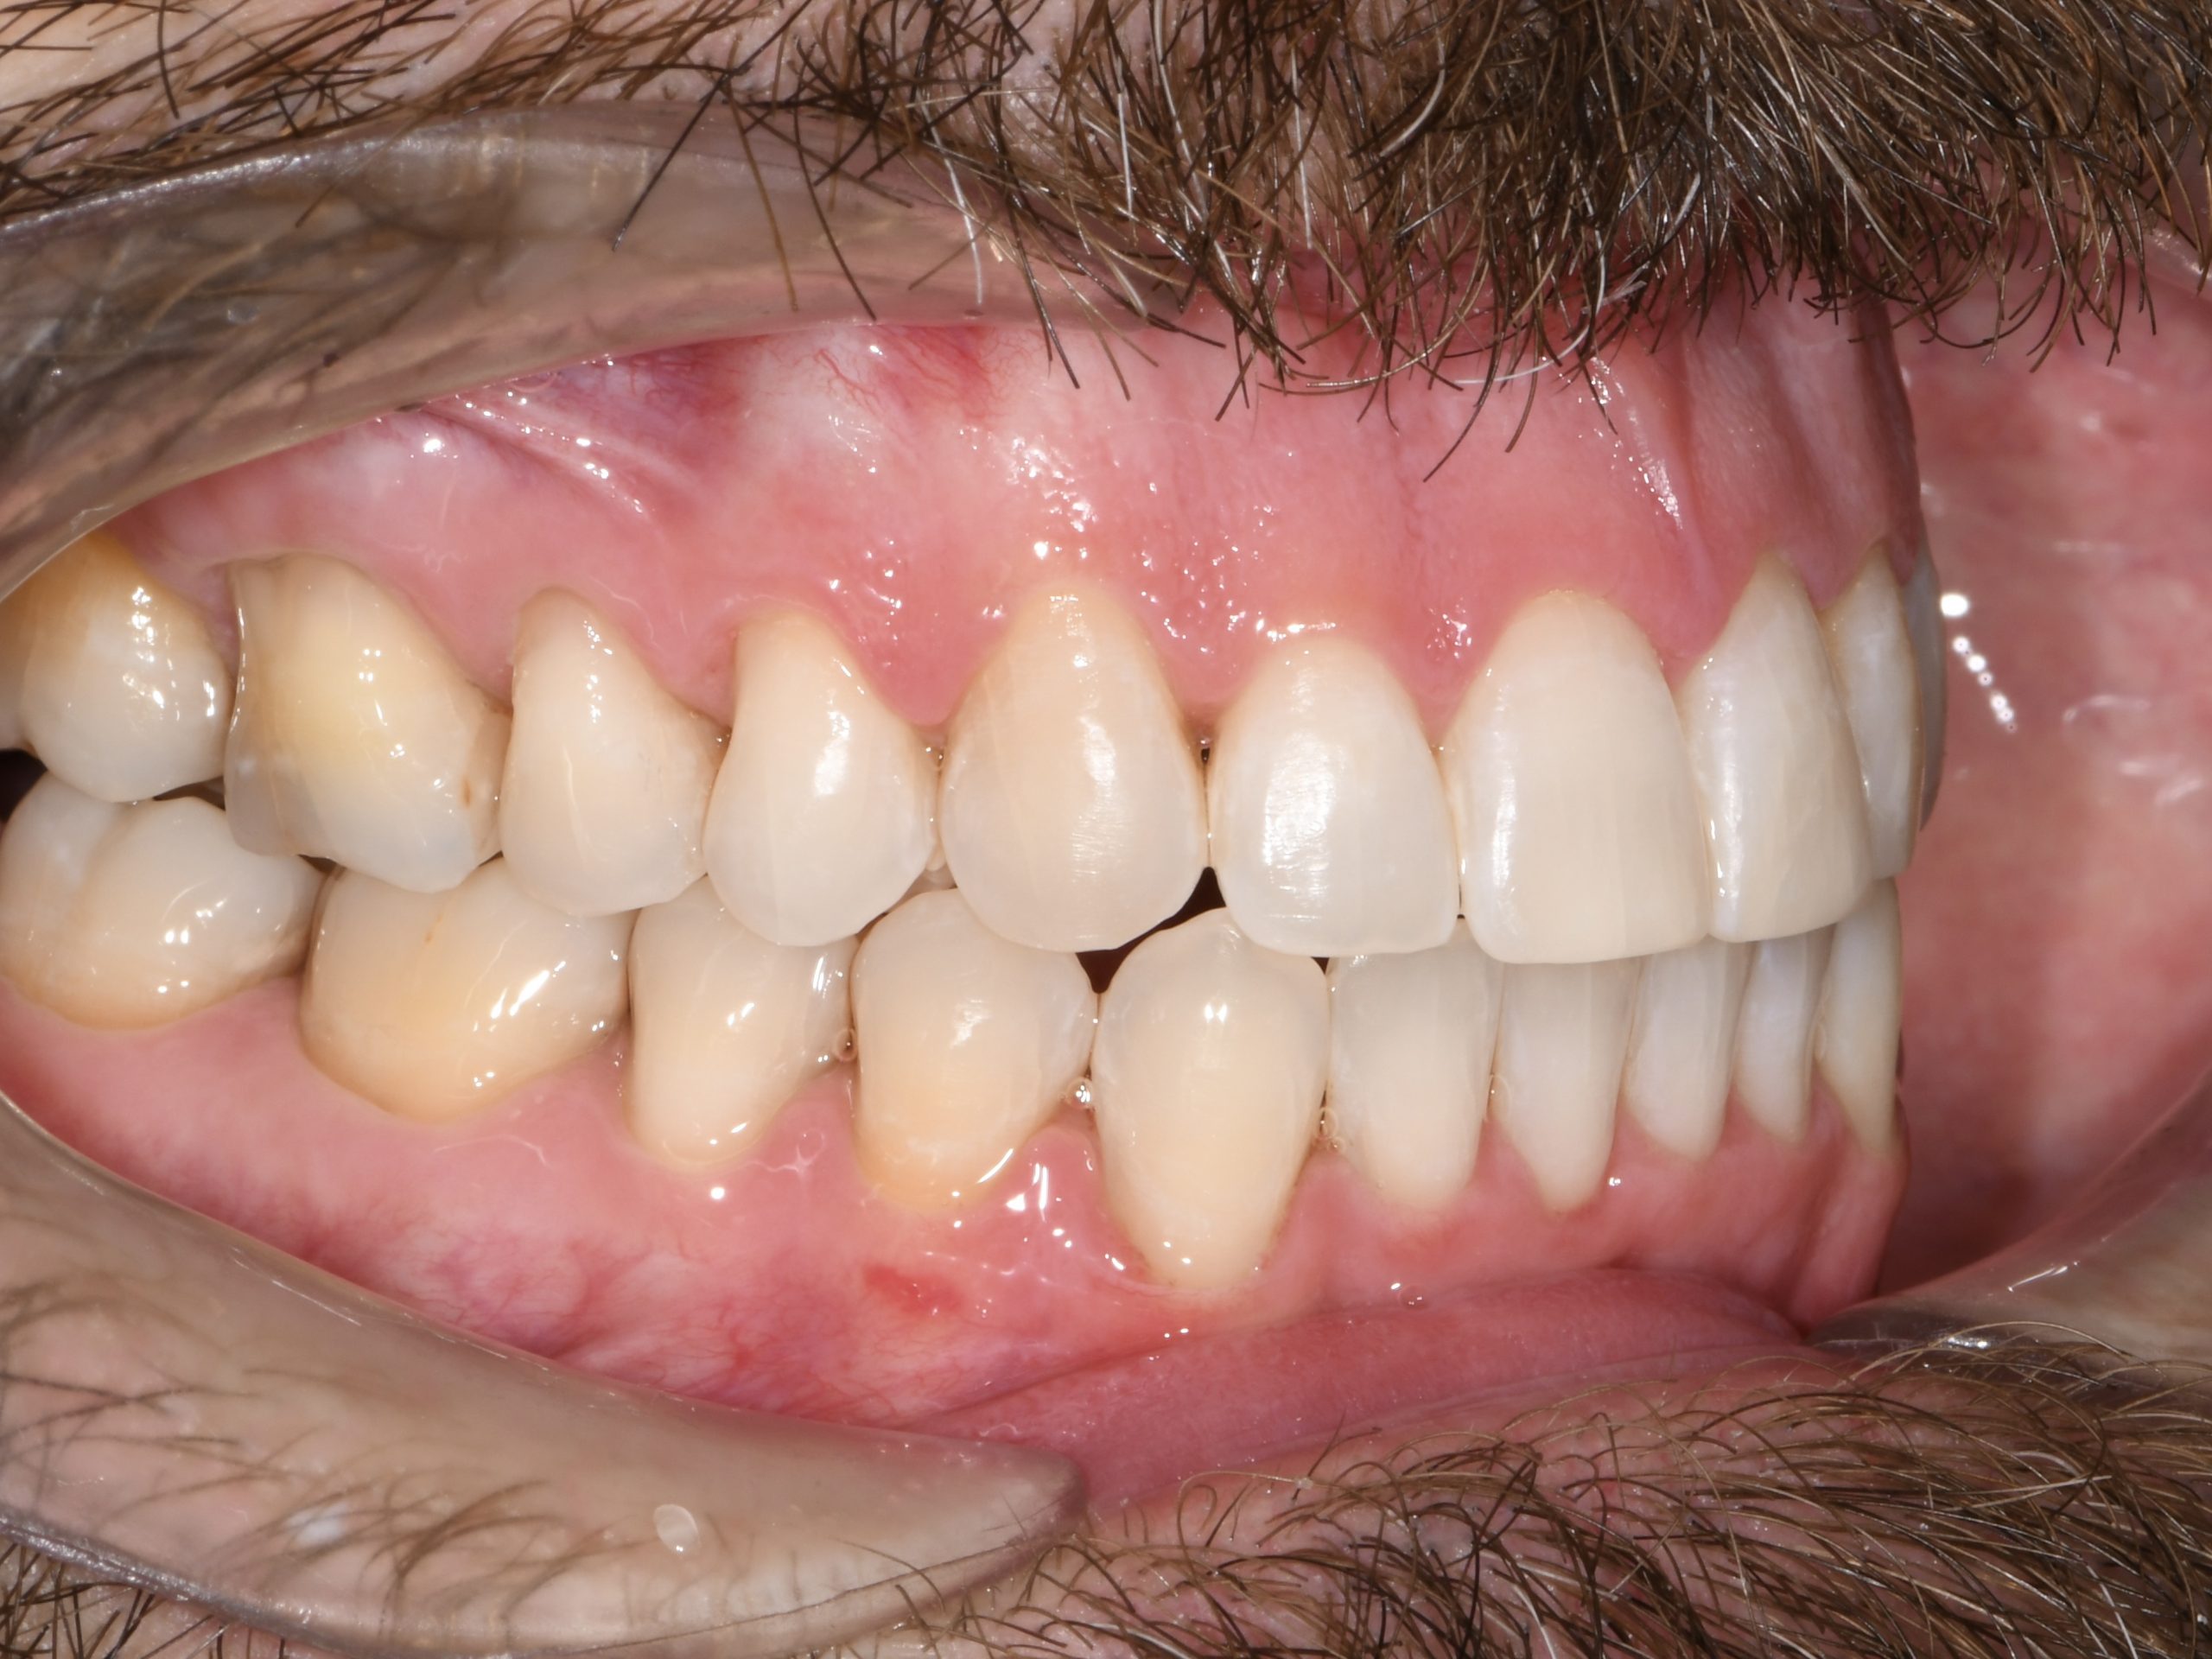

Az elmúlt évekből rengeteg szakmai referenciát tudnánk bemutatni, amelyek különböző fogszabályozási problémákat oldottak meg. Válogatva a több száz esetből, ezen az oldalon olyan képeket, információkat igyekeztünk bemutatni, amelyeknek a segítségével a jövőbeni pácienseinknek azt tudjuk üzenni: A Te fogsorod is lehet gyönyörű!

(Képeket a Pácienseink külön írásos beleegyezésével mutatjuk be!)